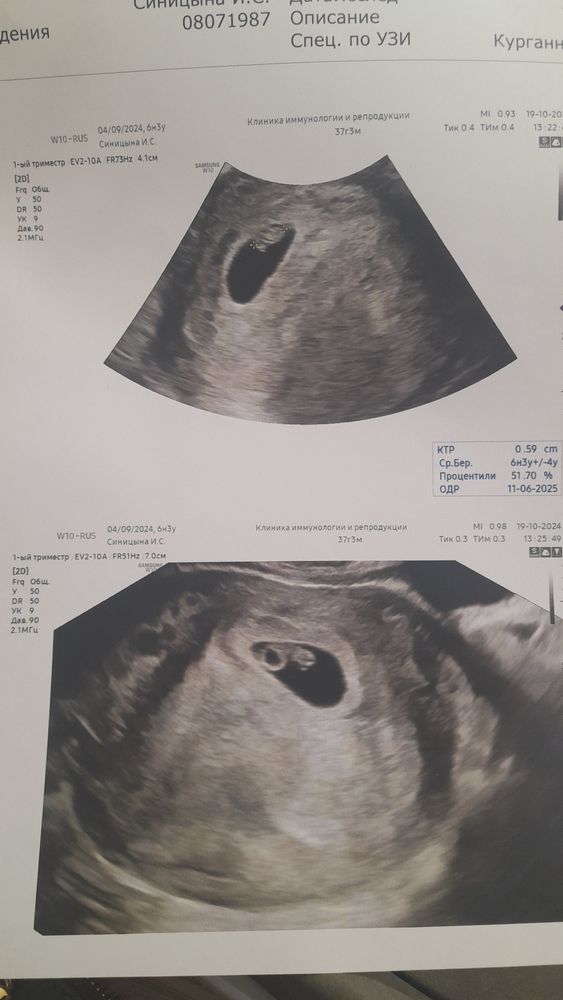

Плодное яйцо отстаёт на неделю - прогнозы???

Девочки, кто сталкивался!!! Вроде все хорошо, мылаша нашли, сердечко послушали. Но плодное яйцо отстаёт на неделю. Кажется, меня это смутило больше, чем врача, он сказал не много отстаёт, поэтому не критично. Интересует Ваш опыт. У кого было? Все хорошо в итоге???

Ничего не отстаёт,по таблице пя 14 мм это 6,2 недели,но вообще это не важно,оно разное может быть и больше и меньше,важна разница между пя и ктр,для благополучной беременности она должна быть не менее 5 мм,у вас разница 14 и 6 между ними 8 мм это полная норма,редко когда встречается и пя и ктр на один срок,вот если б у вас пя было 9 мм,а ктр 6 мм,вот тогда уже прогноз неблагоприятный